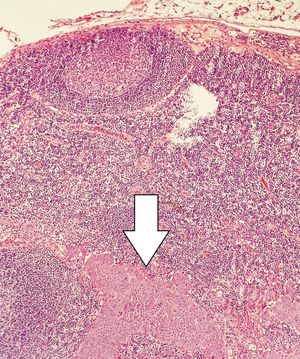

5. 3. 조직 병리학

신경내분비 병변은 세포의 모양보다는 세포가 얼마나 빨리 자라는지를 나타내는 표지에 따라 조직학적으로 등급이 매겨진다. 현재 세계 보건 기구(WHO)는 모든 위장관 및 췌장 신경내분비 종양에 대해 다음과 같은 등급 분류 체계를 권장한다.[36]

유사분열 수와 Ki-67 지수가 서로 다른 등급을 가리킬 경우, 더 높은 등급을 부여하는 수치를 기준으로 삼는다.

G1 및 G2 등급은 신경내분비 종양(NET, Neuroendocrine Tumor)으로 분류되며, 이전에는 유암종(카르시노이드)이라고 불렸다. G3 등급은 신경내분비 암종(NEC, Neuroendocrine Carcinoma)으로 분류된다.

최근에는 G3 범주를 예후(치료 후 경과 예측)를 더 잘 반영하기 위해, 조직학적으로 분화가 잘 된 종양과 분화가 잘 안된 종양으로 더 세분화하자는 제안이 있다.[37]

병리 진단 시에는 우선 현미경으로 세포 형태의 이상 유무를 관찰한다. 또한, 특정 단백질에 반응하는 항체를 이용하여 종양 세포를 식별하는 면역 염색(Immunostaining) 방법을 사용하기도 한다.[106] 면역 염색은 특정 단백질의 존재 유무를 색깔로 나타내어 현미경 관찰을 용이하게 한다.[107] 신경내분비 종양의 병리 진단에 사용될 수 있는 면역 염색 표지자의 예는 다음과 같다.